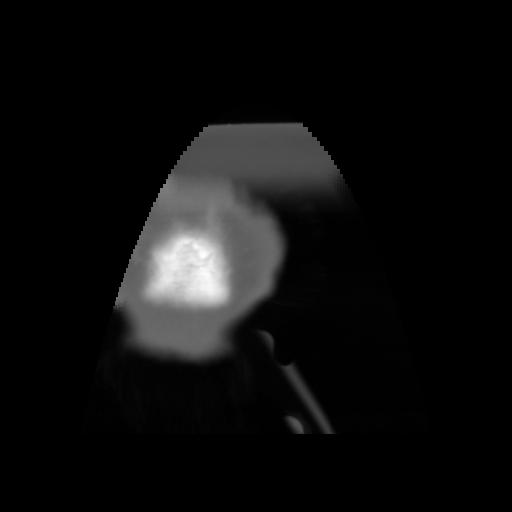

5 CEREBRO,,Coronal,3.000,CEREBRO,Coronal,